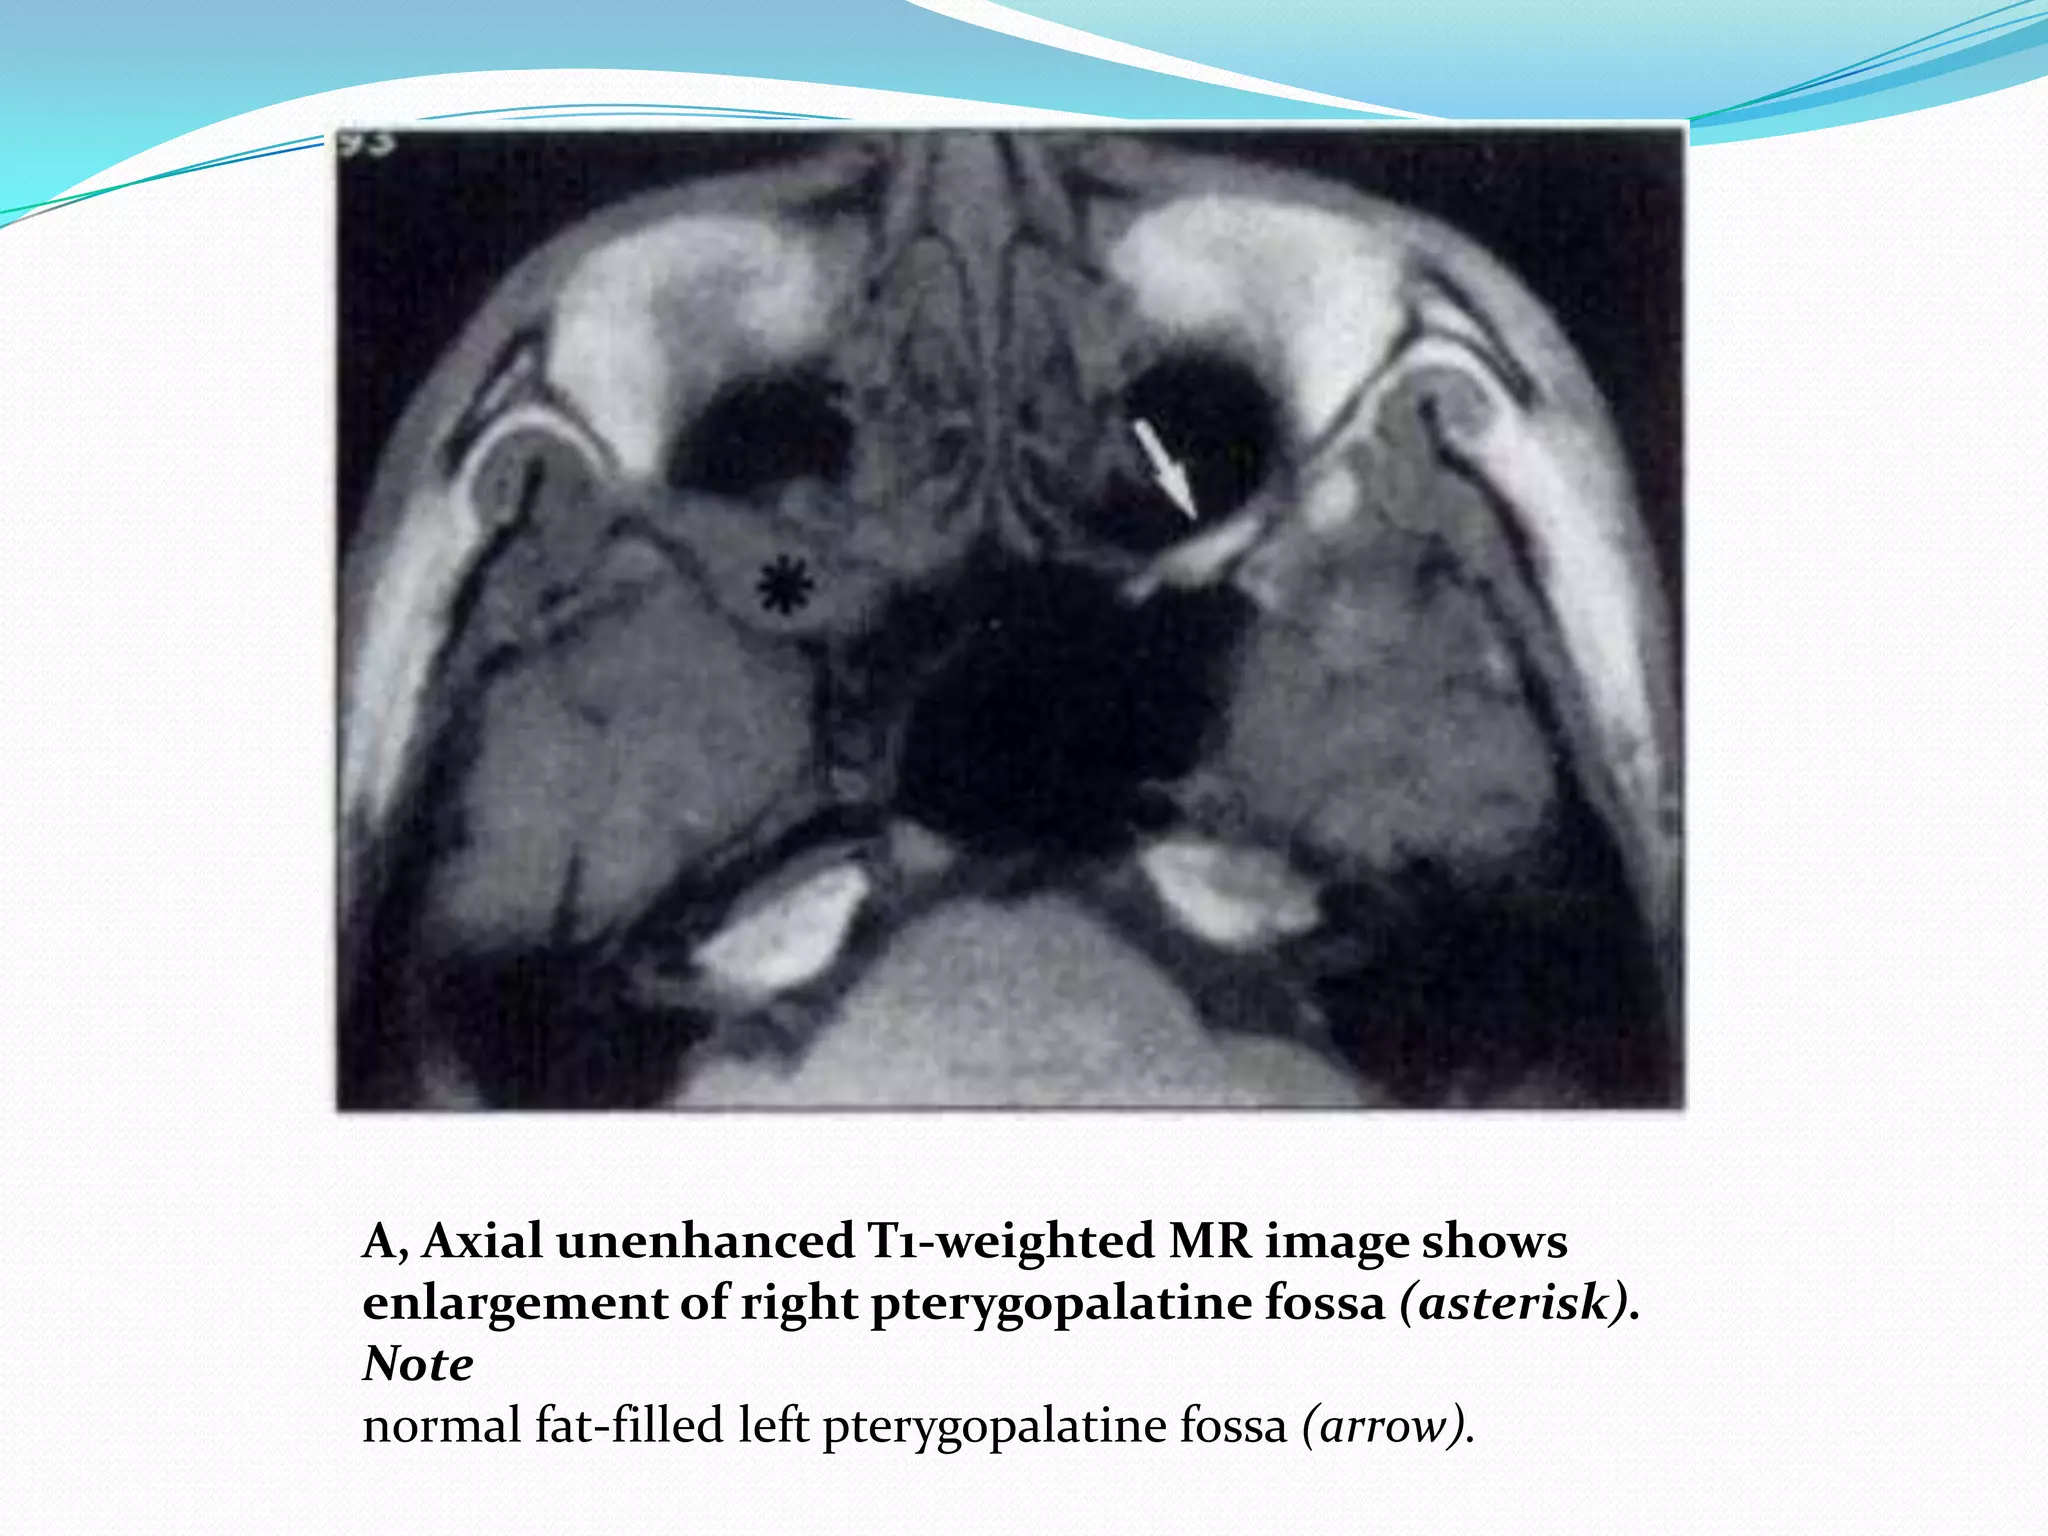

A, Axial unenhanced T1-weighted MR image shows

enlargement of right pterygopalatine fossa (asterisk).

Note

normal fat-filled left pterygopalatine fossa (arrow).